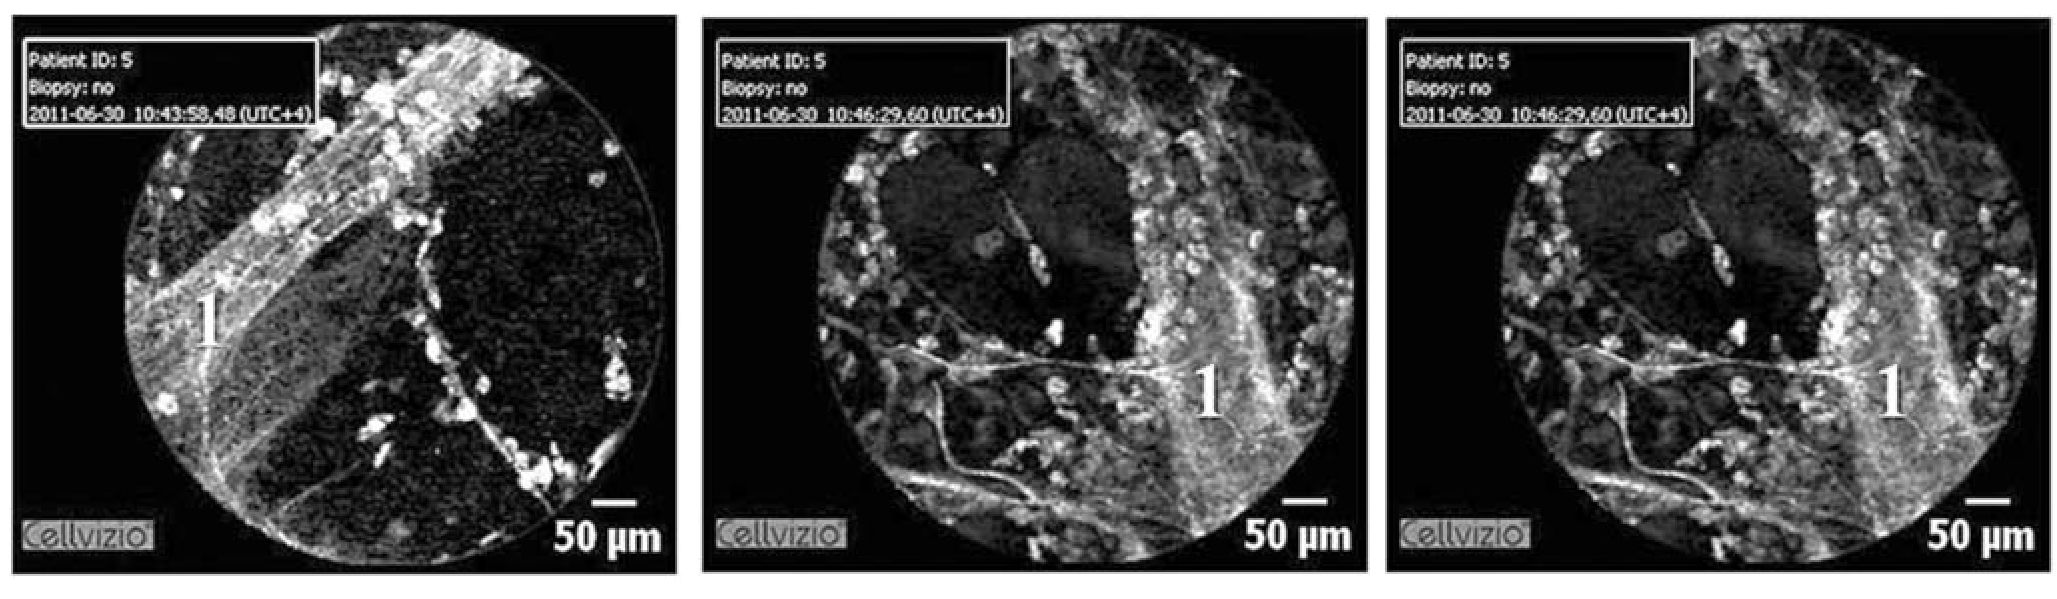

Рис. 2а. Ациноскопия. Терминальная бронхиола с выраженным слоем эластических волокон (1)

При изучении изображений КЛЭМ мы отметили повторяющиеся структуры овальной или округлой формы, не меняющие своего размера, средним диаметром около 200 микрон, что соответствует вестибулярному отделу респираторной бронхиолы 3-го порядка. Важным моментом, позволяющим нам обосновать это суждение, является то, что вслед за изображением стенки бронхиолы при проведении датчика в дистальном направлении визуализируются ячеистые структуры, представленные взаимопересекаемыми волокнами эластина, что довольно часто предваряется овальной структурой, являющейся, судя по всему, вестибулярным отделом или «альвеолярным ртом» (рис. 3).

Поскольку единственным методом получения визуального изображения ацинуса до последнего времени являлась оптическая микроскопия, экстраполяция результатов оптической микроскопии на полученные изображения при КЛЭМ позволяют нам увидеть сходство между выявленными структурами ацинуса и их изменения. Важным аспектом является понимание врачом-морфологом и эндоскопистом т.н. угла осмотра структур (например, бронхиол), имеющих выраженные отличия в трехмерном измерении. В данном случае разница составляет 90. В то же время непосредственно визуализация ацинуса в меньшей степени зависит от угла среза и сопоставление данных КЛЭМ и оптической микроскопии осуществить проще. На правом рисунке (фото при КЛЭМ) хорошо виден развитый слой эластических и коллагеновых волокон терминальной бронхиолы, расположенных в сагиттальной плоскости. Слева стенка терминальной бронхиолы представлена в аксиальной плоскости, имеется хорошо развитый косопоперпечно ориентированный слой эластина и коллагеновых волокон (рис. 2, 2а).